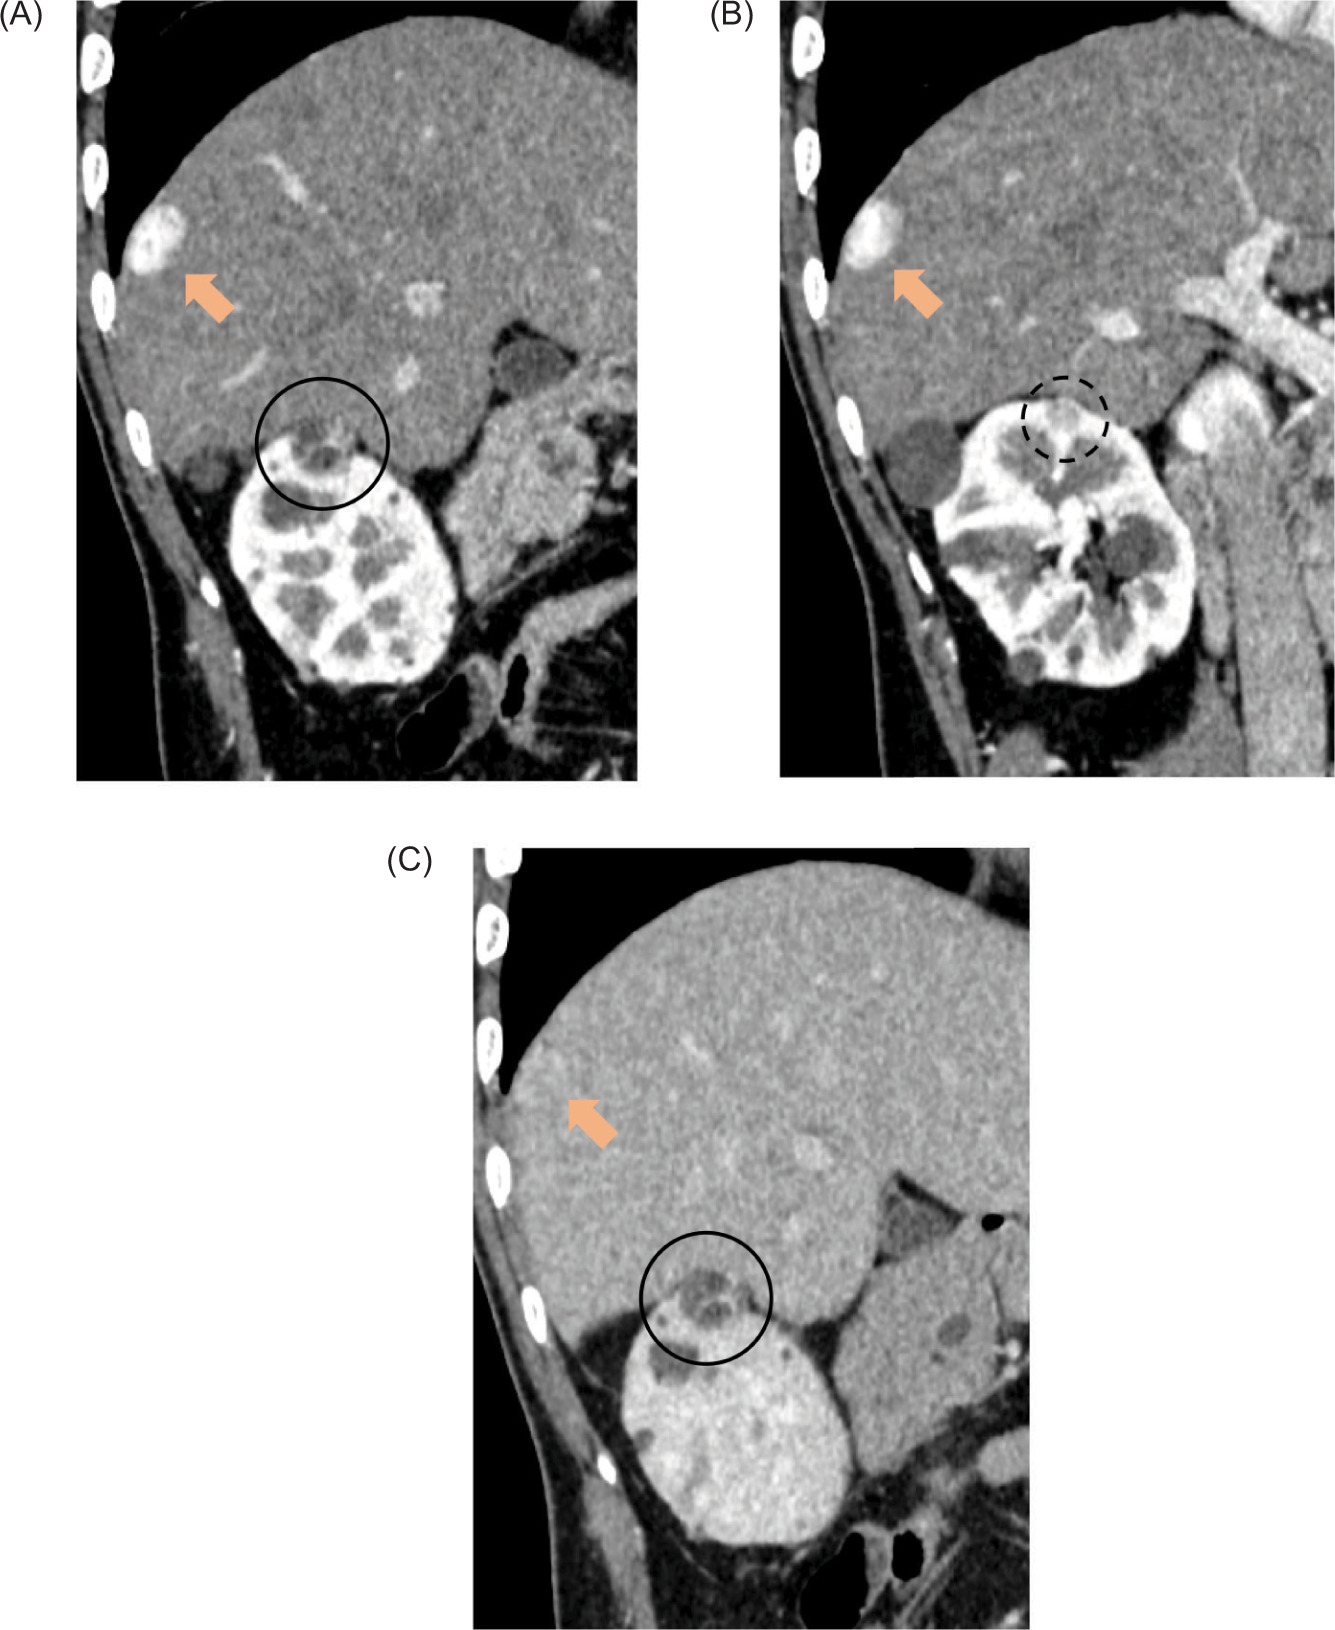

Here, we report the case of a 38-year-old man with VHL diagnosed by genetic testing who presented to our hospital with small right renal nodules, suspected to be RCC. The nodules gradually increased over time and were detected during periodic follow-ups with plain computed tomography (CT) and magnetic resonance imaging (MRI). Therefore, he was referred to our department for further evaluation and treatment of the renal nodules. He was asymptomatic and presented with no other diseases and normal laboratory data. Contrast-enhanced CT and MRI revealed nodules (1.8×1.5 cm and 1.1×1.0 cm in diameter, respectively) on the ventral side of the right kidney (Figure 1). He also had a nodule (2.5×1.7 cm in diameter) contiguous with the diaphragm and compressing the liver from the outside (Figures 1 and 2). The renal nodules had cystic degeneration, heterogeneous early enhancement, and delayed washout, suggesting clear-cell RCC. Moreover, the nodule contiguous with the diaphragm had a contrast pattern similar to that of renal lesions (Figure 1).

Figure 1: Dynamic computed tomography (CT) images (A and B: corticomedullary phase, C: delayed phase, oblique images). CT images revealed nodules with septal enhancement and cystic degeneration, 1.8 cm (circle) and 1.1 cm (dot circle) in diameter on the right renal upper pole. A nodule with early enhancement and delayed washout of 2.5 cm in diameter (arrow) bordering the liver surface was also detected.